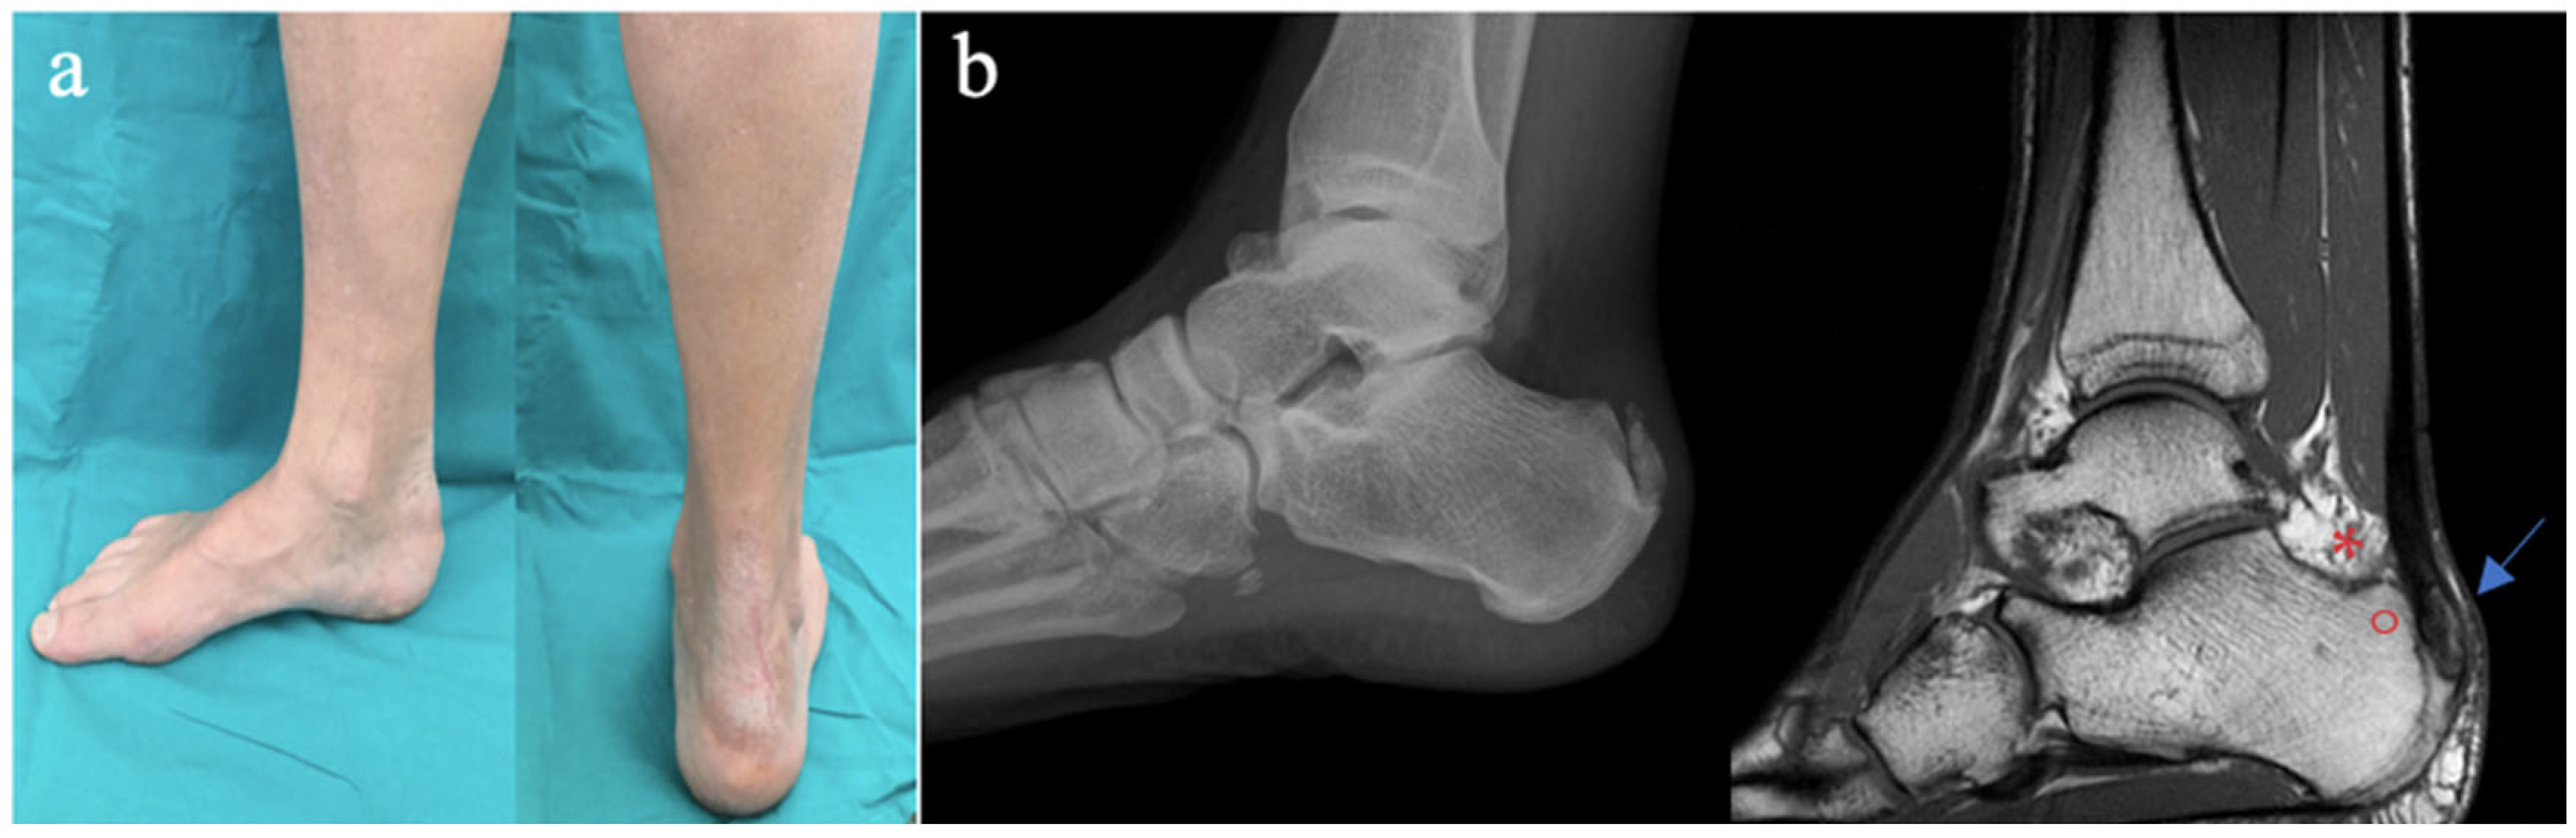

Successful Achilles Tendon Reattachment Using SpeedBridge in Haglund’s Triad Patients